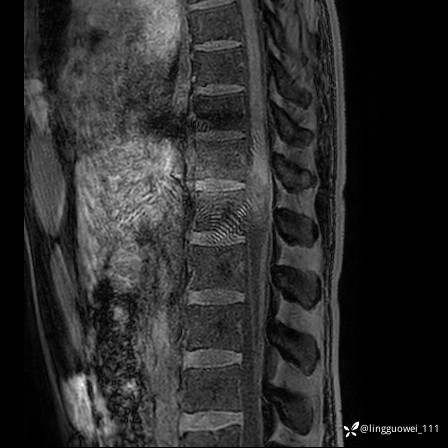

男,38岁,反复腰痛伴双腹股沟区痹痛半年,加重1月。

腰椎MR,注意脊髓异常信号,与伪影鉴别,一不小心就会漏诊

T1WI: